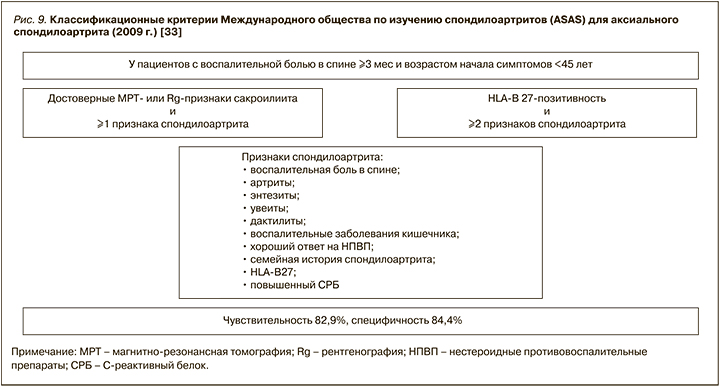

К основным клиническим проявлениям поражения аксиального скелета относятся воспалительная боль в спине и нарастающее ограничение подвижности всех отделов позвоночника. Международное общество по изучению спондилоартритов (ASAS) разработало критерии диагностики для воспалительных аксиальных и периферических поражений суставов (рис. 9) [36].

В соответствии с российской версией модифицированных Нью-Йоркских классификационных критериев анкилозирующего спондилита (2016), это заболевание диагностируется, если у пациента имеются:

- клинические признаки: 1) воспалительная боль в спине (согласно критериям экспертов Международного общества по изучению спондилоартритов (ASAS), 2009); 2) ограничение движений в поясничном отделе позвоночника как в сагиттальной, так и фронтальной плоскостях; 3) ограничение дыхательной экскурсии грудной клетки в сравнении с показателями у здоровых лиц, ПЛЮС;

- определяемый методом визуализации сакроилеит (по данным магнитно-резонансной томографии или рентгенографии).

Анкилозирующий спондилоартрит является прогрессирующим состоянием со структурными поражениями и нарушением движения, что, безусловно, негативно влияет на качество жизни пациентов. В настоящее время диагноз анкилозирующего спондилоартрита считается ранним, если он выставлен на «дорентгенологической» стадии заболевания, т.е. если отсутствует достоверный сакроилеит на рентгенограммах (2-я и более стадия по Келлгрену), либо если он выставлен в течение первых двух лет от начала клинической картины, которую можно соотнести с дебютом болезни [38].